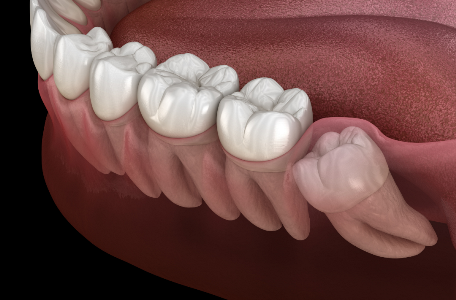

Зубы мудрости – это рудимент. Они достались нам «по наследству» от далеких предков, которые ели более грубую пищу. Их зубы были крупнее, а челюсти – больше.

Сегодня в 90% случаев зубы мудрости требуют удаления, если:

• Зуб не прорезывается полностью – воспаляется десна.

• Зуб растет неправильно, в сторону, в щеку, в соседний зуб.

• Слишком крупные размеры.

• Эстетические проблемы – смещает остальные зубы.